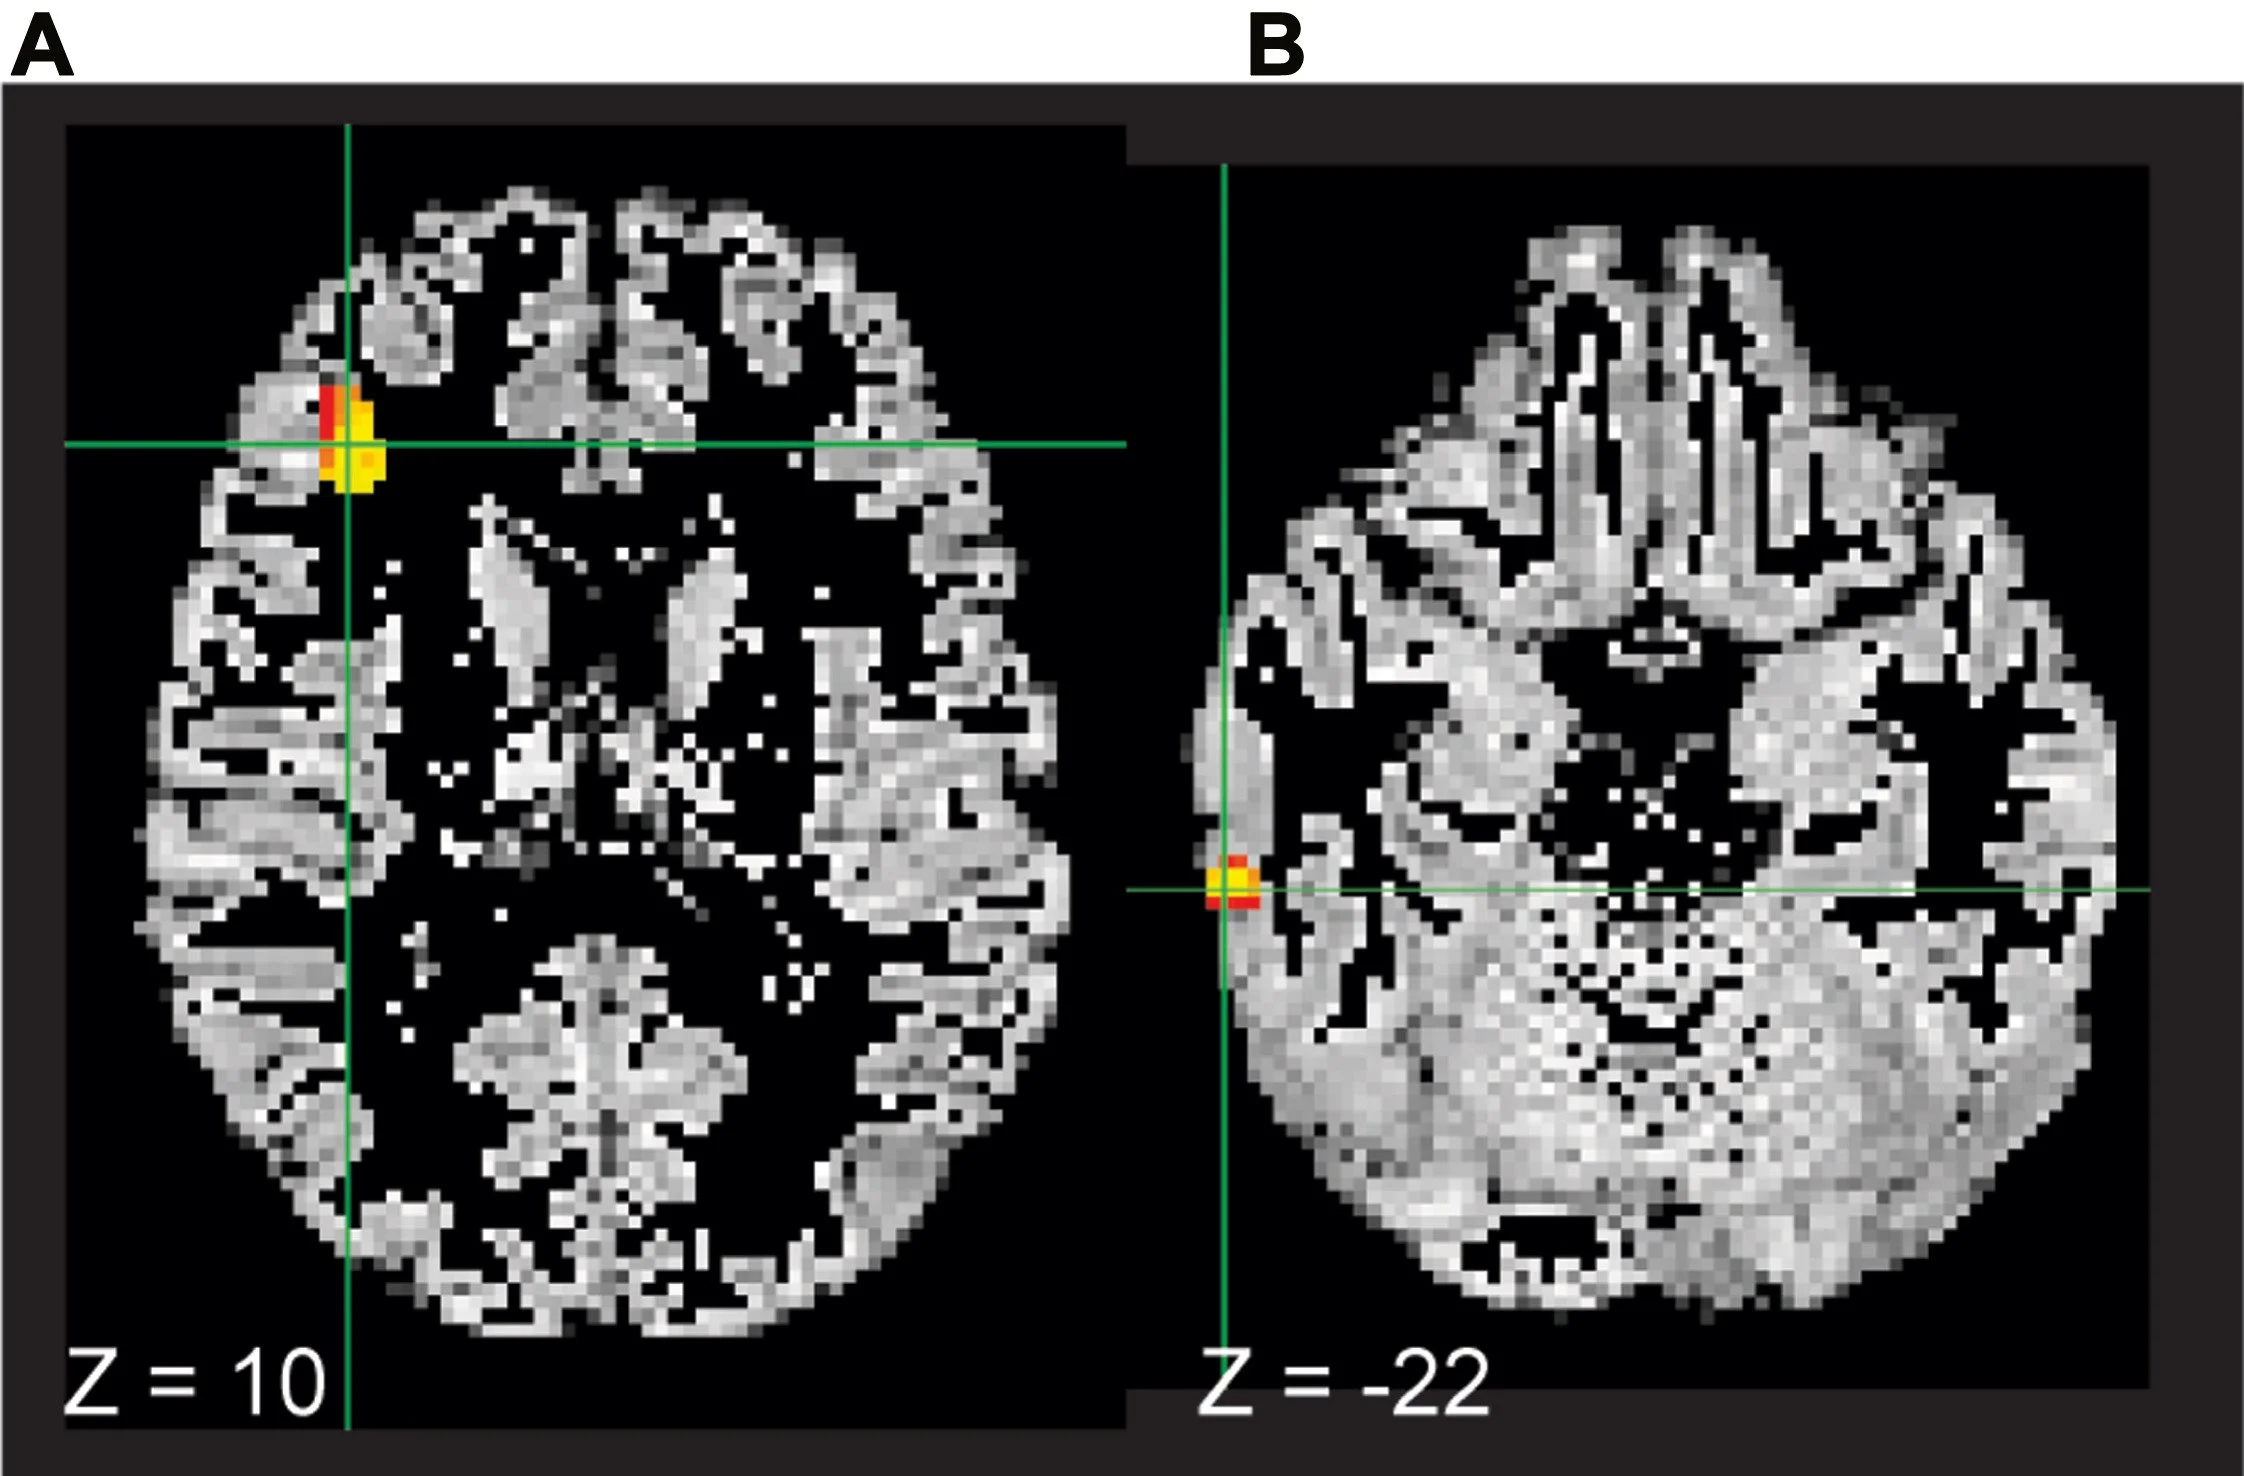

Rumination-focused cognitive behavioral therapy (RF-CBT) works to reduce depressive rumination, and uses functional analysis, exercises, and practice to identify and modify the ruminative habit. This is a pre-registered replication of initial work that is critical in our lab. This replication yielded a significant reduction in rumination response scale scores and a reduction in connectivity between areas of the brain active during self-focused thought, emotion regulation, attention, and language processing. If you would like to read the full article,